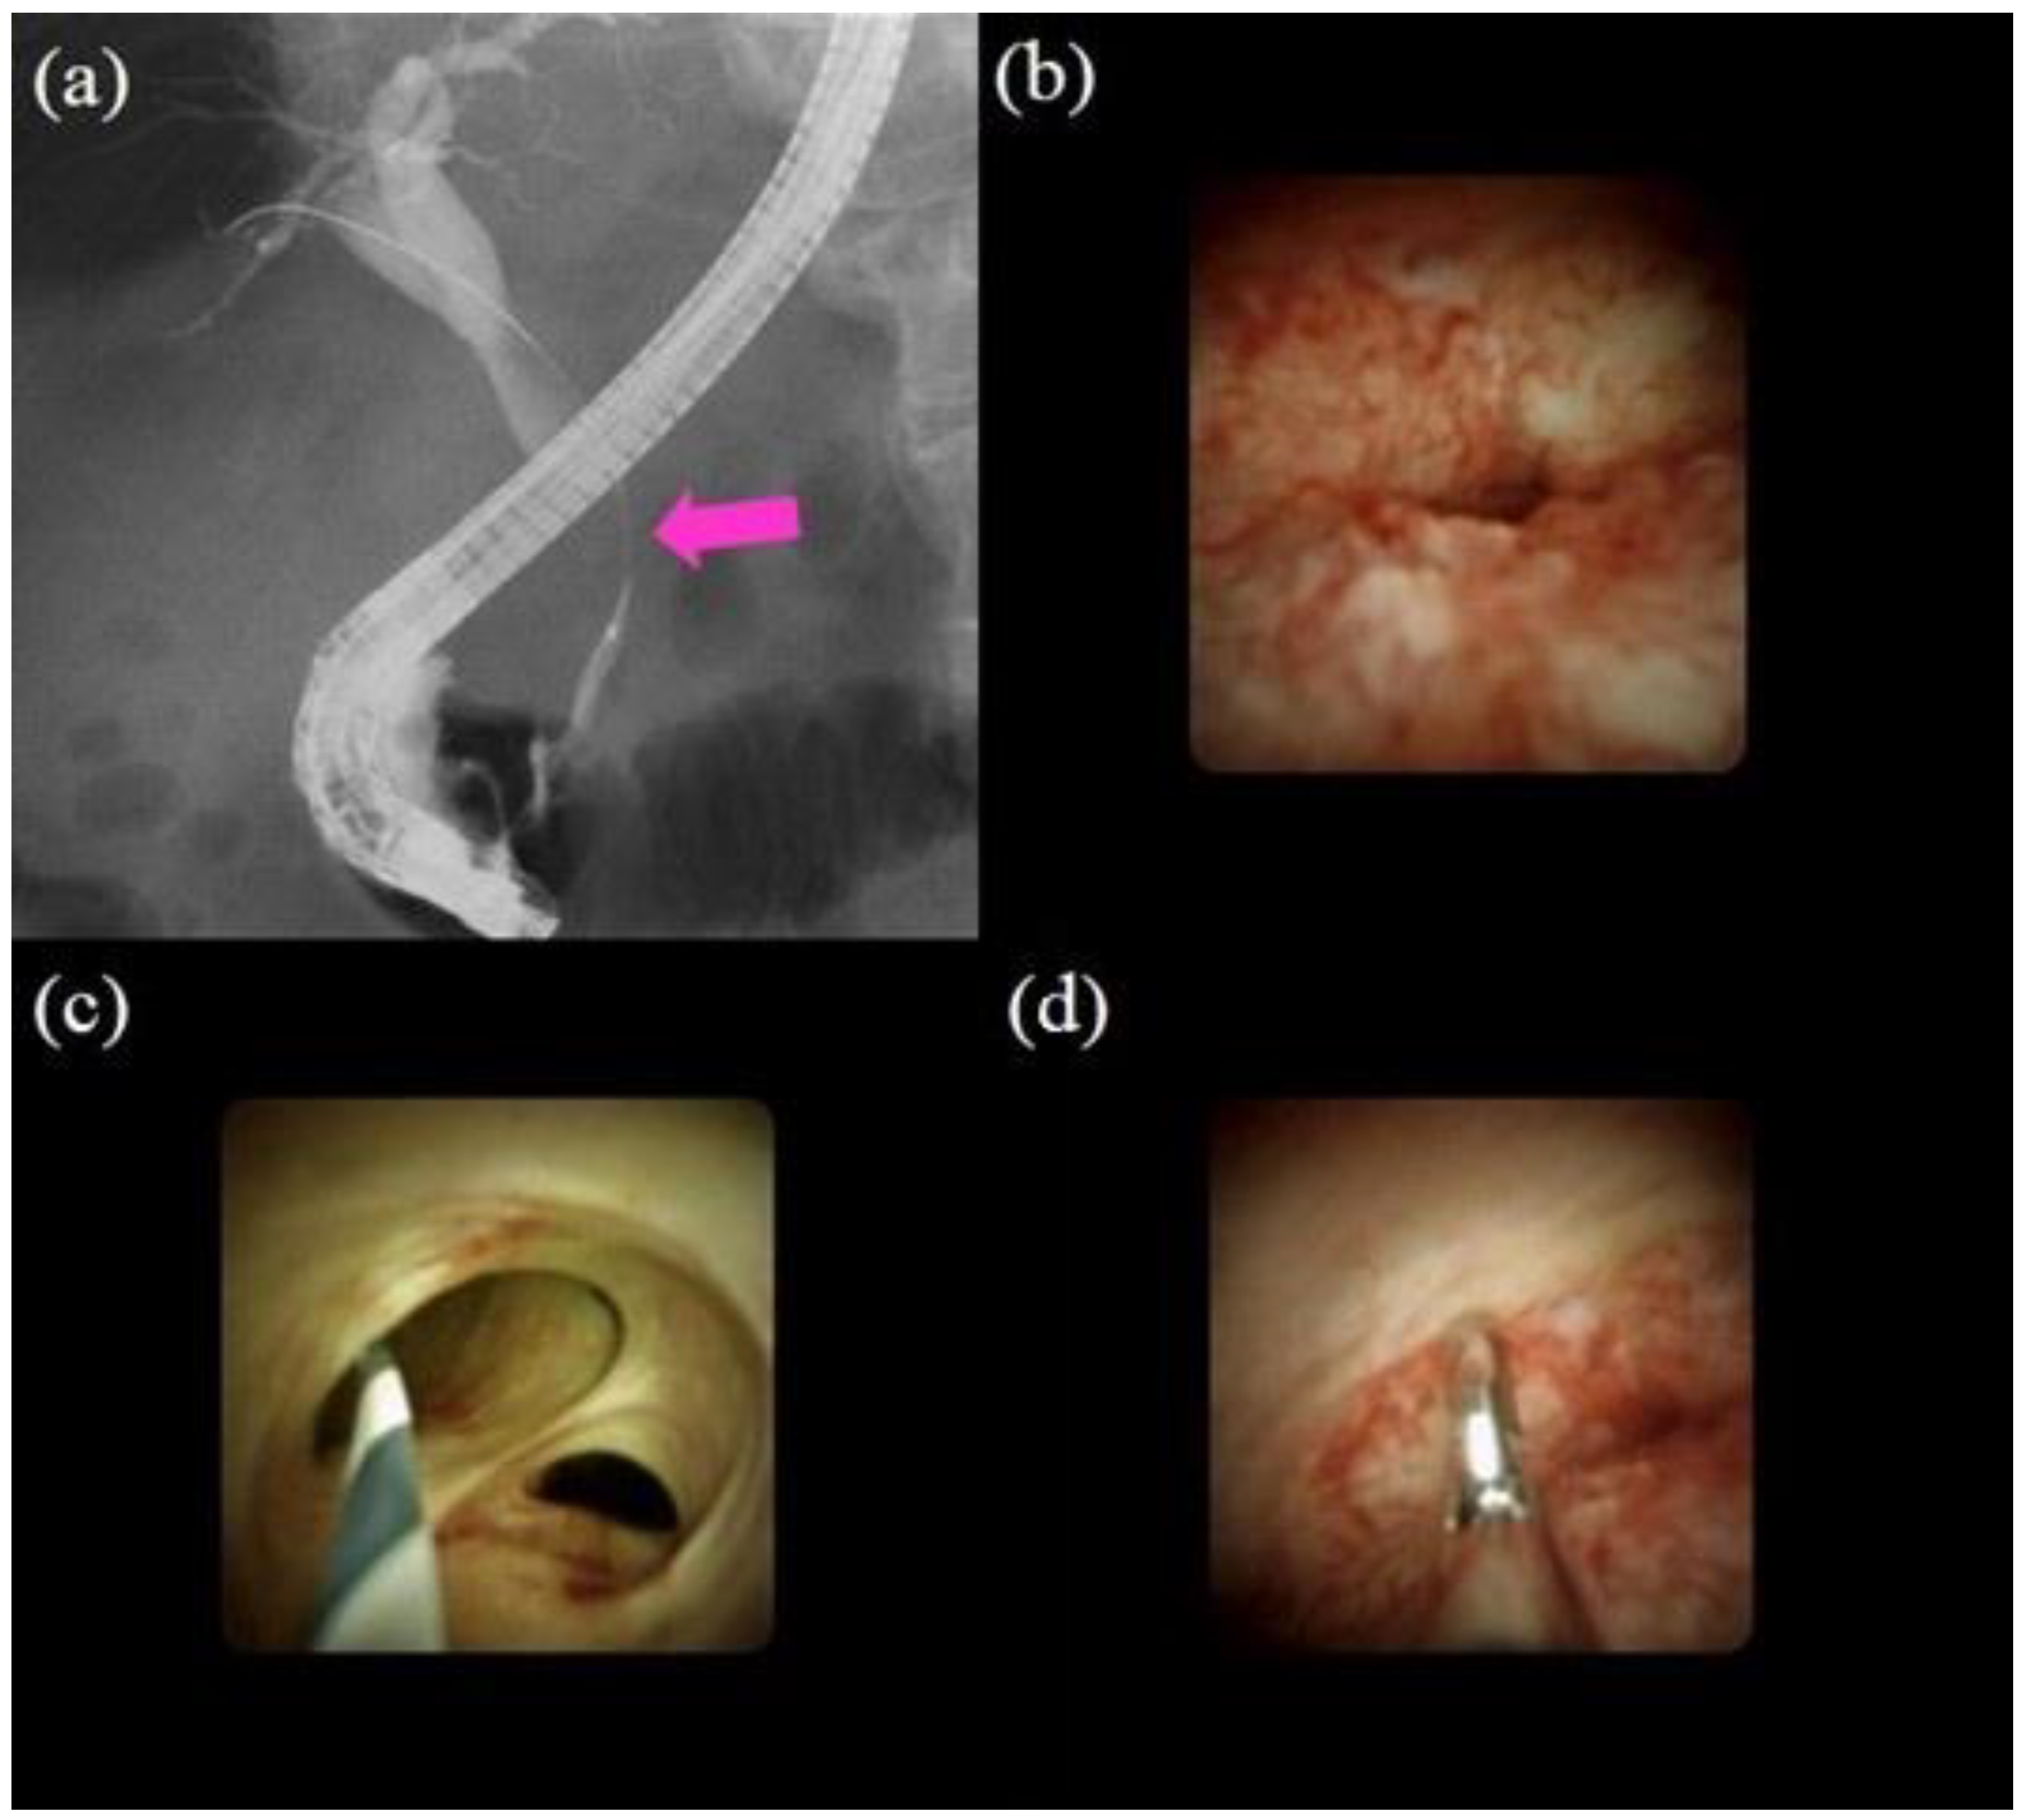

- Nakajima, M.; Akasaka, Y.; Yamaguchi, K.; Fujimoto, S.; Kawai, K. Direct endoscopic visualization of the bile and pancreatic duct systems by peroral cholangiopancreatoscopy (PCPS). Gastrointest. Endosc. 1978, 24, 141–145. [Google Scholar] [CrossRef]

- Chen, Y.K.; Pleskow, D.K. Preclinical characterization of the Spyglass peroral cholangiopancreatoscopy system for direct access, visualization, and biopsy. Gastrointest. Endosc. 2007, 65, 303–311. [Google Scholar] [CrossRef]

- Navaneethan, U.; Hasan, M.K.; Kommaraju, K.; Zhu, X.; Hebert-Magee, S.; Hawes, R.H.; Vargo, J.J.; Varadarajulu, S.; Parsi, M.A. Digital, single-operator cholangiopancreatoscopy in the diagnosis and management of pancreatobiliary disorders: A multicenter clinical experience (with video). Gastrointest. Endosc. 2016, 84, 649–655. [Google Scholar] [CrossRef]

- Seo, D.W.; Lee, S.K.; Yoo, K.S.; Kang, G.H.; Kim, M.H.; Suh, D.-J.; Min, Y.I. Cholangioscopic findings in bile duct tumors. Gastrointest. Endosc. 2000, 52, 630–634. [Google Scholar] [CrossRef]

- Itoi, T.; Neuhaus, H.; Chen, Y.K. Diagnostic Value of Image-Enhanced Video Cholangiopancreatoscopy. Gastrointest. Endosc. Clin. N. Am. 2009, 19, 557–566. [Google Scholar] [CrossRef]

- Itoi, T.; Sofuni, A.; Itokawa, F.; Tsuchiya, T.; Kurihara, T.; Ishii, K.; Tsuji, S.; Moriyasu, F.; Gotoda, T. Peroral cholangioscopic diagnosis of biliary-tract diseases by using narrow-band imaging (with videos). Gastrointest. Endosc. 2007, 66, 730–736. [Google Scholar] [CrossRef]

- Tanisaka, Y.; Ryozawa, S.; Nonaka, K.; Yasuda, M.; Fujita, A.; Ogawa, T.; Mizuide, M.; Tashima, T.; Araki, R. Diagnosis of Biliary Strictures Using Probe-Based Confocal Laser Endomicroscopy under the Direct View of Peroral Cholangioscopy: Results of a Prospective Study (with Video). Gastroenterol. Res. Pract. 2020, 2020, 1–9. [Google Scholar] [CrossRef]

- Kawakami, H.; Kuwatani, M.; Etoh, K.; Haba, S.; Yamato, H.; Shinada, K.; Nakanishi, Y.; Tanaka, E.; Hirano, S.; Kondo, S.; et al. Endoscopic retrograde cholangiography versus peroral cholangioscopy to evaluate intraepithelial tumor spread in biliary cancer. Endoscopy 2009, 41, 959–964. [Google Scholar] [CrossRef]

- Draganov, P.V.; Chauhan, S.; Wagh, M.S.; Gupte, A.R.; Lin, T.; Hou, W.; Forsmark, C.E. Diagnostic accuracy of conventional and cholangioscopy-guided sampling of indeterminate biliary lesions at the time of ERCP: A prospective, long-term follow-up study. Gastrointest. Endosc. 2012, 75, 347–353. [Google Scholar] [CrossRef] [PubMed]